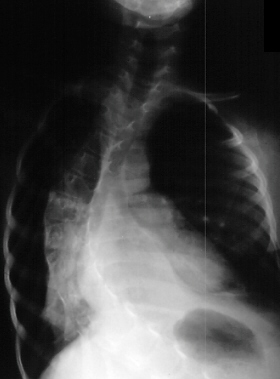

A three year old girl is brought for evaluation because of possible

scoliosis. Her developmental history was of a normal vaginal delivery weighting

8 pound 6 ounce, full term female with no perinatal events and normal intrauterine

movement. She was developing normally until 6 months of age when parents

noticed she stopped moving her legs and lost the ability to roll over.

At that time a work up including muscle biopsy concluded that the diagnosis

was Spinal Muscular Atrophy (SMA). She was managed with outpatient and

inpatient rehabilitation consisting of intensive physical, occupational

and aquatic therapy and the use of long leg braces at age of 2. By age

three there was concern about her spine. Radiographic evaluation at age

of 3 (image 1) and age of 6 (image 2)were done.